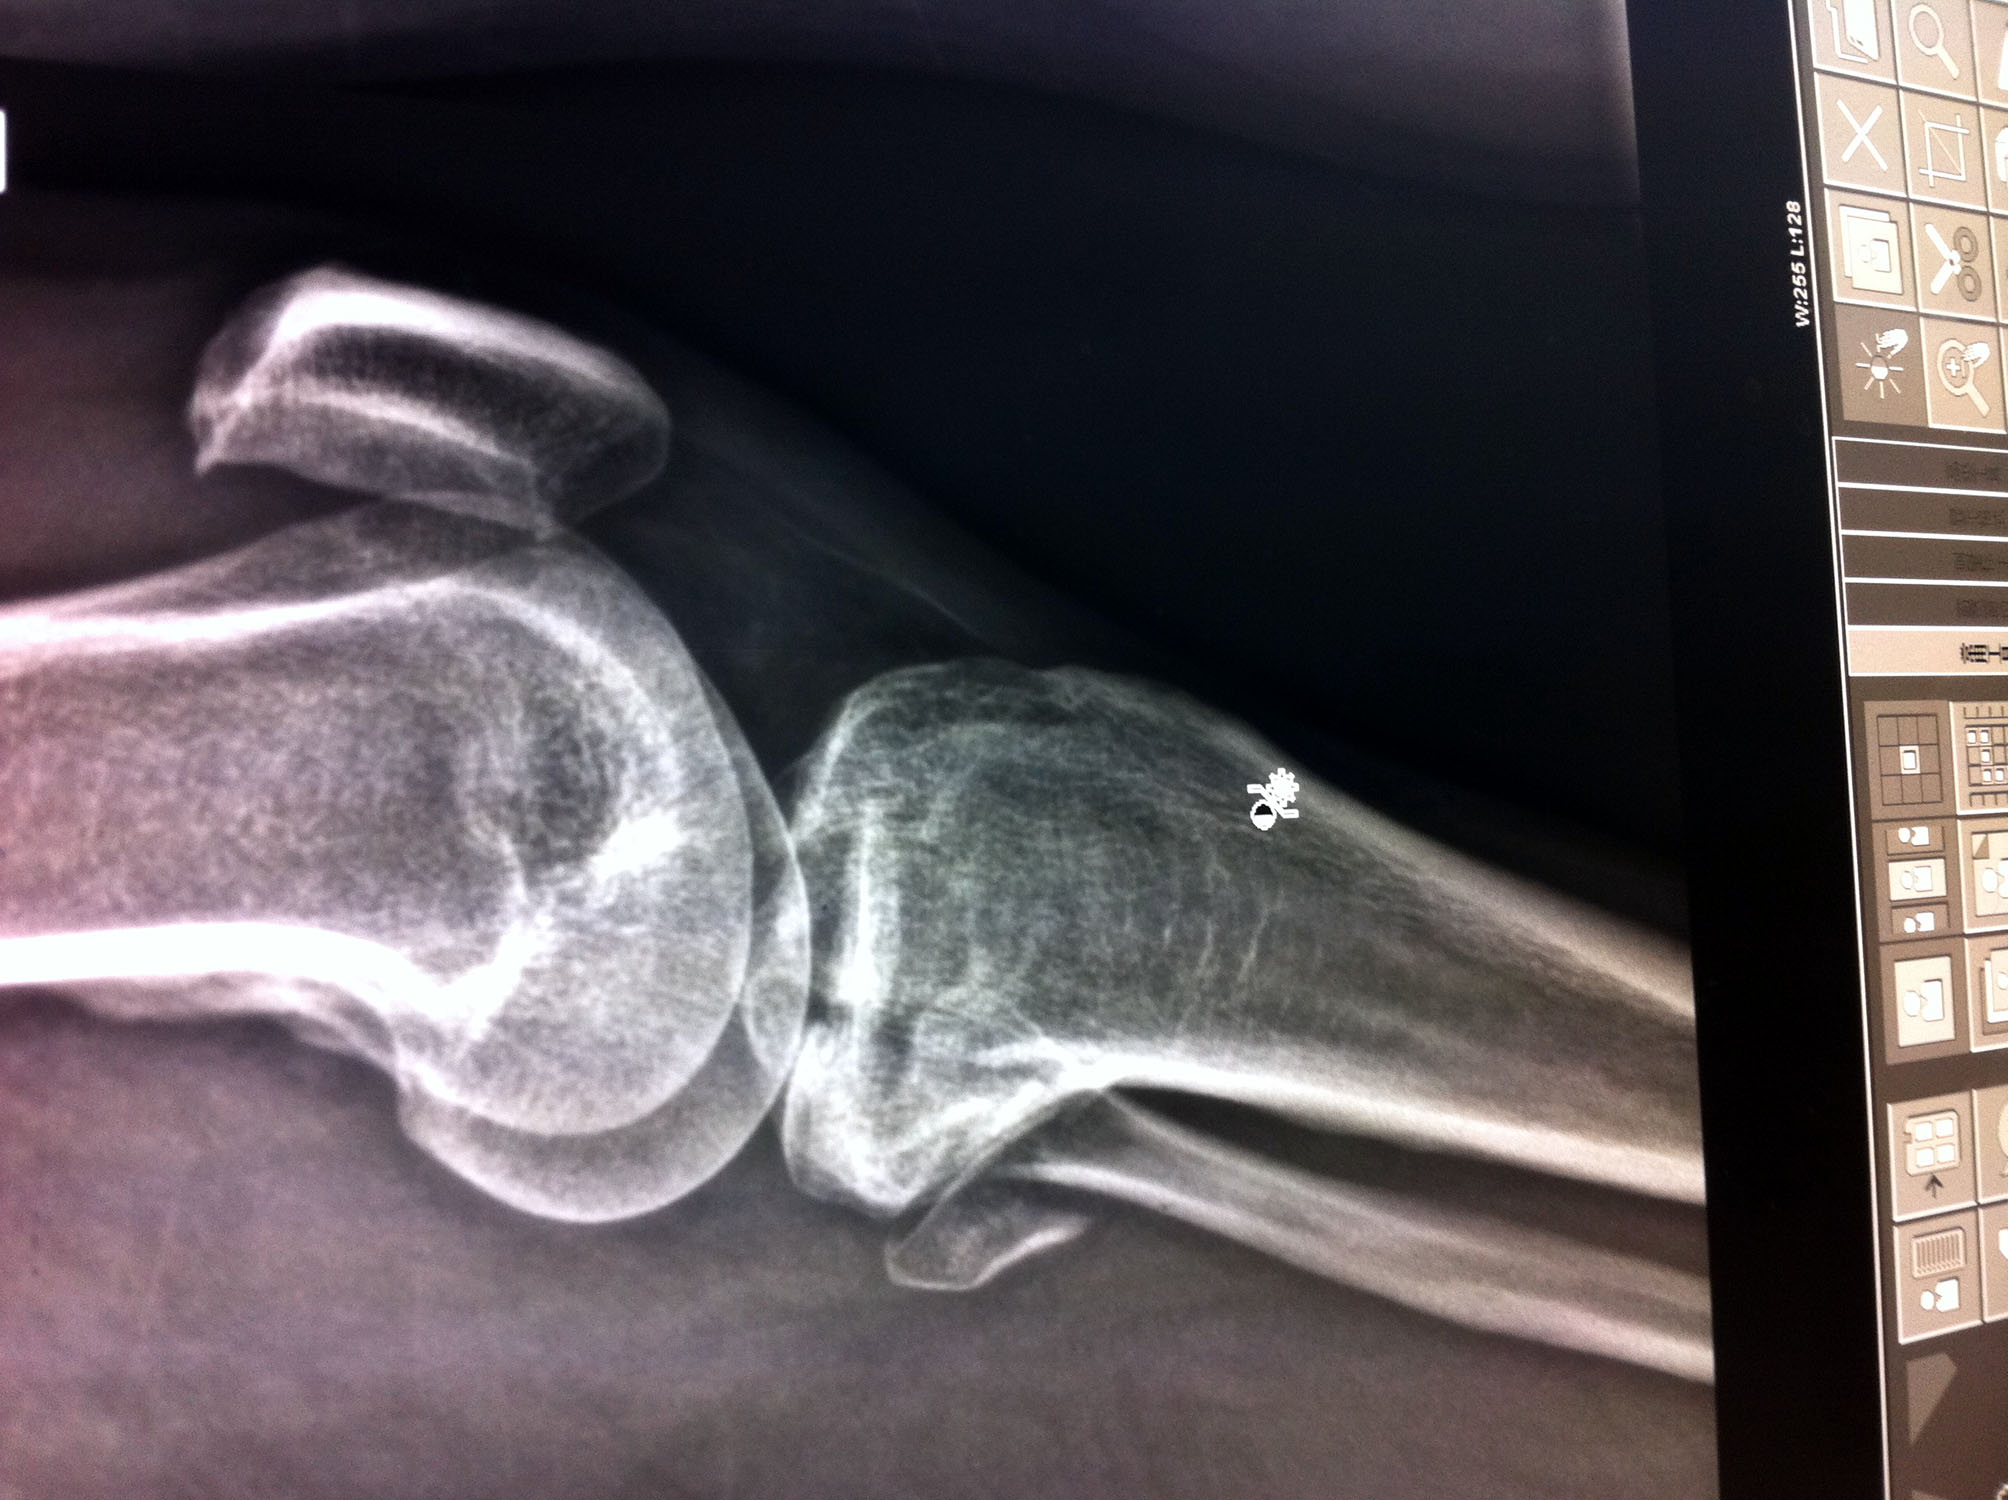

![]() 张定钢左腿被打骨折 | ![]() 张定钢左腿被打骨折 |

张定钢,男、四十八岁,十月二十五日下午被绑架期间,左腿被打骨折,不能行走,用于做生意的面包车,两部手机,家中钥匙、现金约一万六千元,被非法劫走,扣留在李村派出所,家人一直在索要,恶警始终不给,分管的警察的电话:0532-6657661